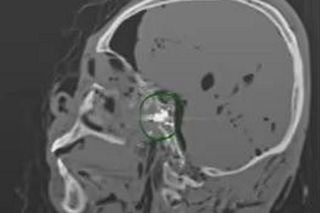

Po trzech miesiącach, w listopadzie 2024 roku Suchir Balaji został znaleziony martwy w swoim mieszkaniu w San Francisco w dzielnicy Mint Hill. Miał poważną ranę głowy, obok niego leżał pistolet, który legalnie nabył w styczniu 2024 roku. Sprawę oficjalnie uznano za oczywiste odebranie sobie życia. Ale rodzice mężczyzny, Poornima Ramarao i Balaji Ramamurthy nie uwierzyli w to. Byli pewni, że sprawa jest podejrzana, bo syn nie wykazywał żadnych skłonności depresyjnych i miał plany na przyszłość, umawiał się m.in. na rozmowy kwalifikacyjne i dostawał bardzo intratne propozycje. Jak pisze "Daily Mail", zlecili niezależne ekspertyzy dwóm lekarzom radiologom. Medycy nie wiedzieli, czyje prześwietlenie czaszki oglądają. Orzekli, że pacjenta trafiły dwie kule, a na jego ciele znaleźli obrażenia, o których oficjalna autopsja milczy.

"Druga kula prawdopodobnie weszła przez usta, nie widać wyraźnej rany wlotowej, ale utkwiła w tylnej części gardła u podstawy czaszki/stożka" - napisał w raporcie dr Daniel Cousin z Radsurity w Weston na Florydzie. Jak podkreśla matka 26-latka, ekspertyza ujawniła obrażenia języka, które nie mogły powstać przy strzale w czoło. Do tego Balaji miał złamaną kość policzkową i uraz z boku głowy oraz ranę na kolanie. Zastrzelił się dwa razy i jeszcze pobił? To nie wszystko. Rodzice komputerowca zlecili też badania toksykologiczne, które ujawniły, że w chwili śmierci w organizmie 26-latka były alkohol i ślady tak zwanej pigułki gwałtu. Matka i ojciec Suchira Balaji nie mają wątpliwości - "to była napaść". Zapowiadają ujawnienie większej ilości materiałów.